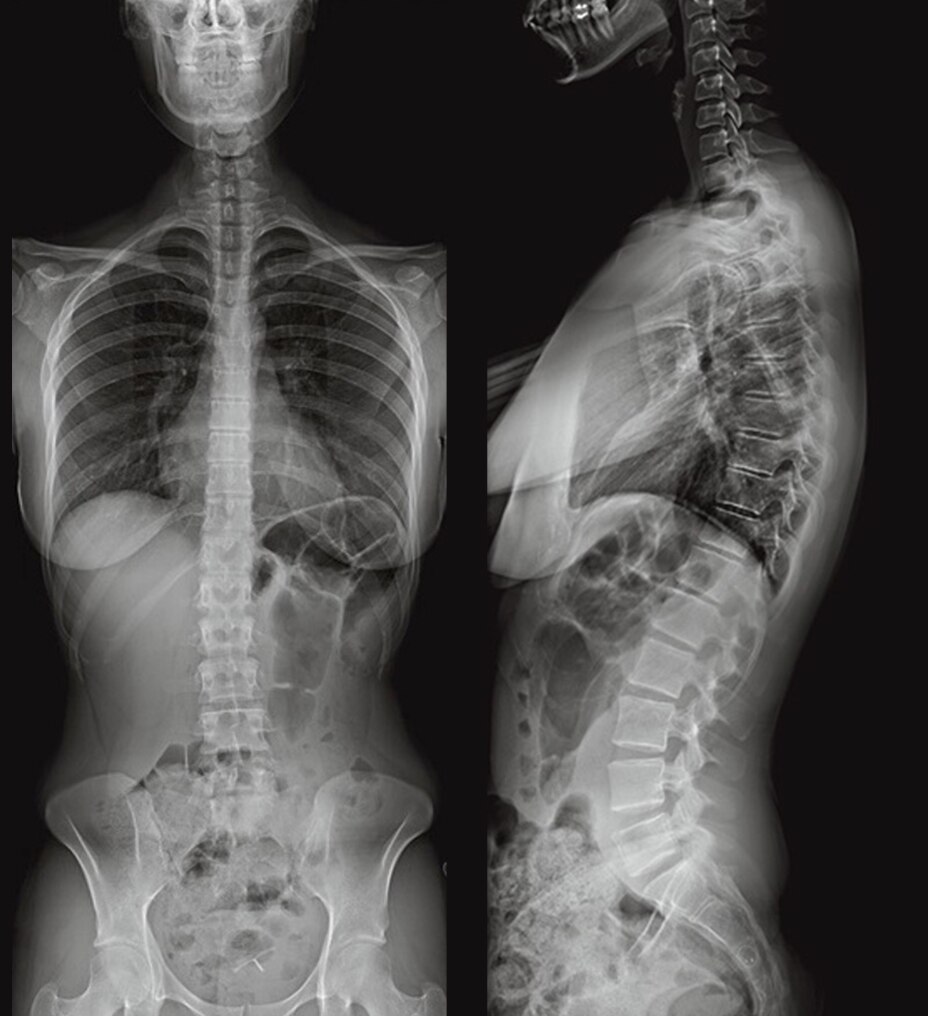

Birden fazla uygulamada çok yönlülük

Revolution Ascend; rutin, kardiyak, büyük bedenli hasta, Acil Servis ve girişimsel dahil olmak üzere çoğu ortama yönelik özelliklere sahiptir.

Revolution Ascend, önceki nesil GE BT tarayıcılara kıyasla tünelin içindeki hasta alanını1 yüzde 22 artırmak için daha düşük bir masa pozisyonu ile 75 santimetre genişliğindeki yeni bir gantri tasarımını birleştirir. Bu artış, hastalara daha rahat bir BT tarama deneyimi için daha fazla alan sağlar. Bu yeni daha geniş tünel tasarımı ile Revolution Ascend, sınıfının en kısa geometri tasarımıyla en geniş gantri açıklığını sağlayarak1 BT'yi büyük bedenli hastaların yanı sıra daha küçük bir gantriye yerleştirilemeyecek kadar hassas olabilecek travma vakaları için de kullanılabilir hale getirir.